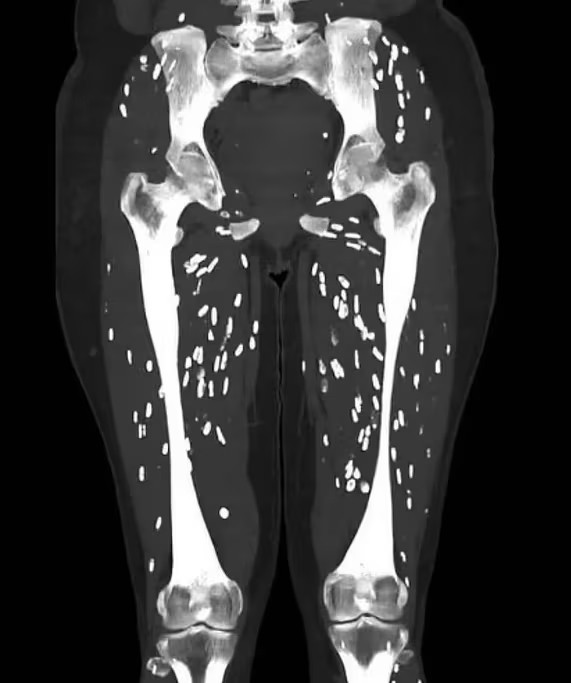

Tuy nhiên, xu hướng này vẫn gây ra mối lo ngại. Ngày 28/8, Tiến sĩ Sam Ghali, bác sĩ cấp cứu tại Đại học Florida Health Jacksonville (Mỹ), đăng một tấm ảnh đáng báo động. Hình chụp CT cho thấy chân của một bệnh nhân chứa đầy nang sán, giống như hạt gạo, kéo dài từ xương đùi đến dưới đầu gối. Tiến sĩ Ghali cảnh báo: "Để tránh bệnh sán dây, bạn không bao giờ được ăn thịt lợn sống hoặc nấu chưa chín".

Chụp CT của một bệnh nhân được chẩn đoán mắc bệnh sán lợn. Ảnh: X